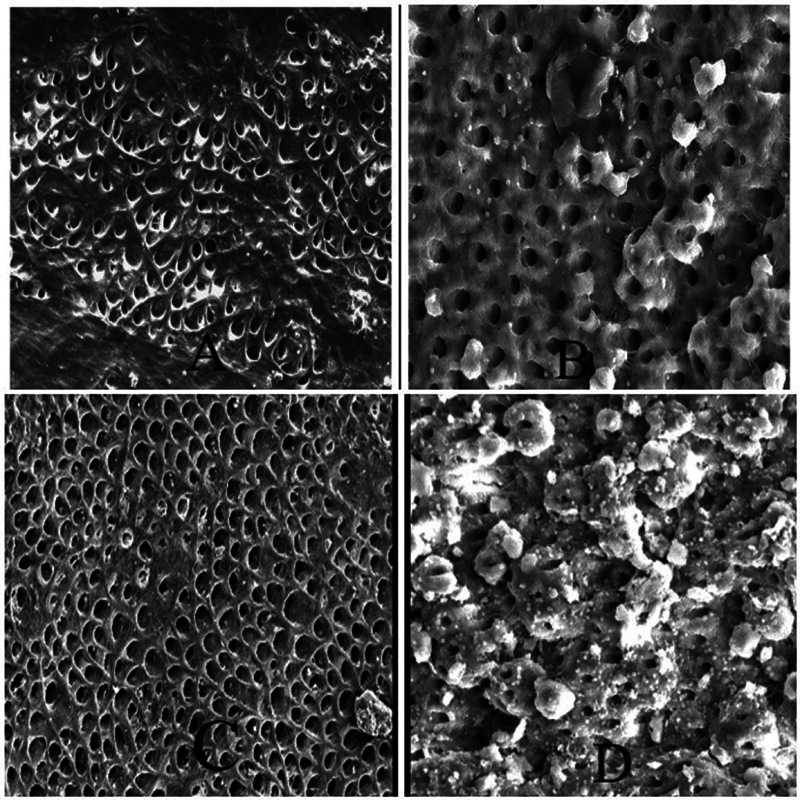

This article compares the effect of ultrasonic, sonic activation of intracanal heated 3% sodium hypochlorite and laser-activated 3% sodium hypochlorite (NaOCl) on root canal cleanliness using scanning electron microscope.Eighty-eight permanent mandibular premolars were extracted and decoronated to obtain 14 mm of standardized root length. Working length was calculated and canals were prepared till size 25/0.04. Samples were randomly divided into four groups according to the method of irrigation employed (n = 22)-group A: passive ultrasonic irrigation (PUI) of 3% intracanal heated NaOCl, group B: sonic activation of 3% intracanal heated NaOCl, group C: activation of 3% NaOCl by diode laser, and group D: conventional needle irrigation (CNI). Samples were split into two halves and the presence of debris at these regions was graded under scanning electron microscope. The chi-square test was employed to assess significant differences in cleanliness scores and pairwise comparisons using the Dunn test were performed to identify specific group difference. A p-value of < 0.05 was kept as level of significance for all analysis.Group A and group B showed maximum cleanliness in middle third as compared with apical third. Group C (laser) showed better cleanliness in apical third as compared with middle third. While group D (CNI) irrigation showed the lowest cleaning efficiency both in the middle third and apical third.It was concluded that PUI with intracanal heating of 3% NaOCl and diode laser activation of 3% NaOCl can be recommended as a potential irrigant activation strategy to effectively clean inaccessible areas of the root canal system.